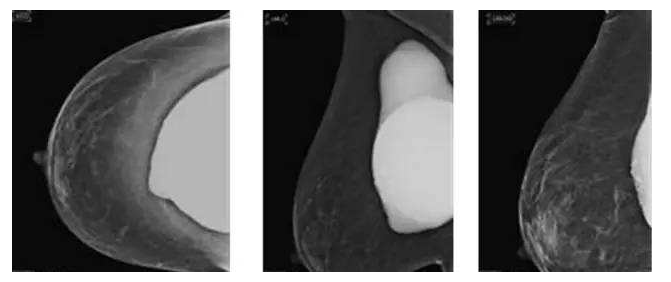

假体隆胸10年后将面临什么样的问题?

假体隆胸手术发展至今已有几十年历程,随之时代的发展,医学的进步,现代隆胸技术在不断升级,假体质量也在不断提高。现代信息的广泛传播,也让受众对于隆胸手术的了解全面化。一台成功的隆胸手术可以维持10年的时间,那么为什么是10年成为了隆胸的关键时期?10年后隆胸的人会面临怎样的问题?

因为假体质量不同、医生操作方式不同、个人体质存在差异,所以具体的存放时间无法被预估。所以假体隆胸10年后,应每年进行B超、核磁共振检查,以确保假体的完整性和安全性,排除并发症,如遇问题,可尽早进行处理。

假体老化最常出现的现象,比如囊壁钙化,渗漏,甚至破裂,还会随着人体组织的老化出现下垂问题。

囊壁钙化:硅胶假体在胸部存放时间过长,在硅胶和自身组织包膜之间,就有可能形成钙化沉淀。轻微的钙化不会对人体造成伤害,无需在意。但如果钙化出现较大的结块,而且集中出现在假体周围,便需要做组织取出或手术。

假体渗漏、破裂:囊膜皱褶经反复运动而老化破裂,后期渗漏或破裂,有纤维囊挛缩或急性炎症现象。假体破裂的发生率虽然很低,当假体出现明显的手感变化,形态的变化,那么这个时候就可能出现了假体的破裂,如果出现假体破裂就需要置换假体。

假体松弛下垂

如果出现假体隆胸变软下垂的问题可能是假体置入层次的问题,假体如果是放在胸部腺体下,它会随着自体的胸部往下垂而一起下垂,如果假体放在胸大肌下,那么就会出现腺体往下走,而假体不往下走,就有可能形成四个胸部的情况。